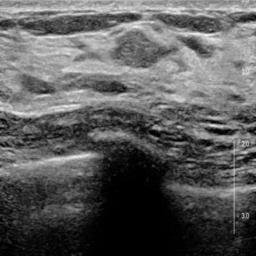

Ultrasonography is an important routine examination for breast cancer diagnosis, due to its non-invasive, radiation-free and low-cost properties. However, it is still not the first-line screening test for breast cancer due to its inherent limitations. It would be a tremendous success if we can precisely diagnose breast cancer by breast ultrasound images (BUS). Many learning-based computer-aided diagnostic methods have been proposed to achieve breast cancer diagnosis/lesion classification. However, most of them require a pre-define ROI and then classify the lesion inside the ROI. Conventional classification backbones, such as VGG16 and ResNet50, can achieve promising classification results with no ROI requirement. But these models lack interpretability, thus restricting their use in clinical practice. In this study, we propose a novel ROI-free model for breast cancer diagnosis in ultrasound images with interpretable feature representations. We leverage the anatomical prior knowledge that malignant and benign tumors have different spatial relationships between different tissue layers, and propose a HoVer-Transformer to formulate this prior knowledge. The proposed HoVer-Trans block extracts the inter- and intra-layer spatial information horizontally and vertically. We conduct and release an open dataset GDPH&GYFYY for breast cancer diagnosis in BUS. The proposed model is evaluated in three datasets by comparing with four CNN-based models and two vision transformer models via a five-fold cross validation. It achieves state-of-the-art classification performance with the best model interpretability.